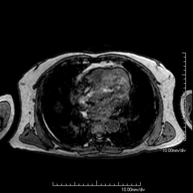

Prova diagnòstica no invasiva que consisteix en l'obtenció d'imatges d'alta definició anatòmica del tòrax mitjançant l'ús d'un camp electromagnètic i ones de ràdio (amb un emissor i un receptor). No utilitza radiació ionitzant. Està indicada en aquelles lesions pulmonars en les quals s'ha de descartar si hi ha infiltració del mediastí o de la paret toràcica, per diferenciar si una lesió toràcica és sòlida o quística, etc. En alguns casos caldrà emprar contrast paramagnètic (Gadolini) per completar l'estudi. - RM de Paret Toràcica

Prova diagnòstica no invasiva que consisteix en l'obtenció d'imatges d'alta definició anatòmica del tòrax mitjançant l'ús d'un camp electromagnètic i ones de ràdio (amb un emissor i un receptor). No utilitza radiació ionitzant. Està indicada en aquelles lesions pulmonars en les quals s'ha de descartar si hi ha infiltració del mediastí o de la paret toràcica, per diferenciar si una lesió toràcica és sòlida, quística, etc. En alguns casos caldrà emprar contrast paramagnètic (Gadolini) per completar l'estudi. - RM d'Abdomen